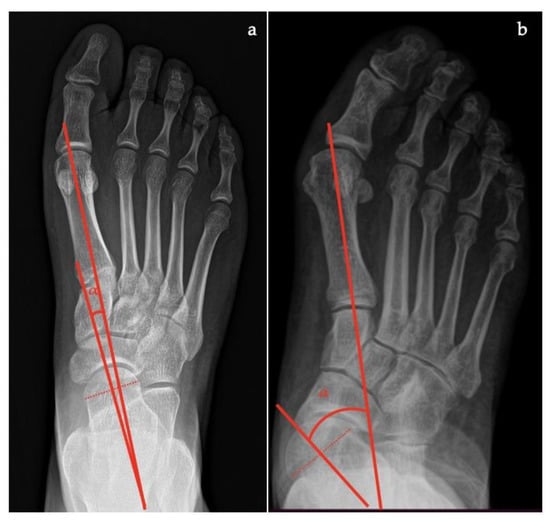

- Talar–first metatarsal angle, between the lines drawn along the long axis of the talus and the first metatarsal (normal 0°, flatfoot: mild >4°, moderate >15°, severe >30°) (Figure 1);

- Talonavicular coverage angle, between the line that joins the medial and lateral articular margins of the talus, and the line that joins the medial and lateral articular margins of the navicular, it represents forefoot abduction (normal, <7°; flatfoot, >7°) (Figure 2);